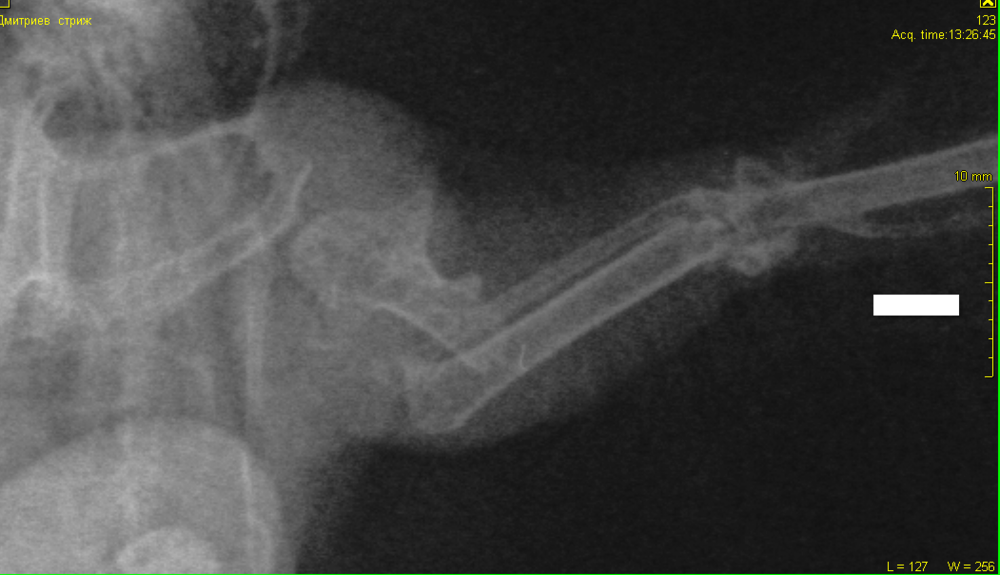

Доброго времени суток. В г. Самара подобрали взрослого стрижа на улице, оттопыривает левое крыло, но машет ими всегда, "пытается улететь" кормим вдвоём через силу сверчками (с рук пока не ест). Сделали рентген (лежит на спине). Подскажите, пожалуйста, это перелом? Если да - то что делать? Есть хоть какой-то шанс на лечение и место где делают операции? Пишите сюда или звоните 8-964-976-37-94. (Перезвоню, если звонок междугородний) Заранее спасибо!

1.png

разрушен полностью локтевой сустав. птица не полетит. никакая операция, реабелитация в этом случае не поможет. пмж или усыпление.